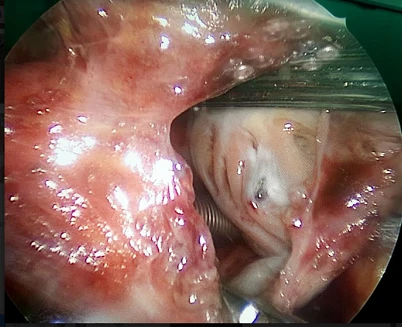

Dị vật nằm trong tim bệnh nhân được tìm thấy qua hình ảnh nội soi.

Ngày 22-8 vừa qua, bệnh nhân đã được mổ nội soi lấy dị vật trong nhĩ phải, nằm sát đường đi của động mạch vành phải.

“Trước khi mổ, chúng tôi đã cho người nhà biết tim là bộ phận nhạy cảm, không thể dể dàng tách mở như nhiều bộ phận khác. Trong hơn 20 phút đầu, các bác sĩ lần theo đường mạch máu và chúng tôi đã rất sung sướng khi chạm được đến dị vật để lấy nó ra. Người bệnh sống sót được hơn 45 năm với dị vật trong tim là một điều kỳ diệu, khoa học chưa giải thích được” - BS Định chia sẻ.